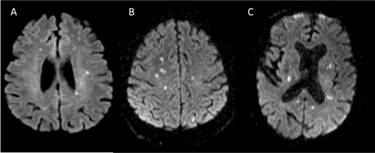

A 73-year-old male presented with sudden-onset right upper limb weakness and pedal oedema lasting for 5 days. He had a history of chronic kidney disease (CKD) on maintenance dialysis, diabetes mellitus, hypertension, coronary artery disease (CAD), and a prior left hemiparesis following an old cerebrovascular accident (CVA) with minimal residual deficit. An MRI of the brain revealed multiple small non-hemorrhagic diffusion-restricted areas in the bilateral cerebral hemispheres, gangliocapsular region, pons, and cerebellar hemisphere, suggesting an embolic stroke (Figure 1A). During his hospital stay, the patient experienced paroxysmal atrial fibrillation, which was managed with beta-blockers. Surprisingly, a 2D Echo revealed vegetation at the tip of the right atrioventricular valve, leading to empirical antibiotics and antiplatelet therapy. Blood cultures grew Enterococcus faecalis, and antibiotic treatment was adjusted. Subsequently, the patient deteriorated requiring inotropes and NIV. He also underwent intermittent slow low-efficiency dialysis (SLED). Due to financial constraints, the patient was transferred to another facility for further management.

A 73-year-old male, presented with reduced responsiveness for 1 day. He was status post mitral valve replacement, on anticoagulation. MRI brain done showed multiple areas of diffusion restriction bilateral cerebral hemispheres, basal ganglia and cerebellar hemispheres (Figure 1B). Transthoracic echocardiogram showed dilated left and right atria, prosthetic valve with no worsening regurgitation. Blood cultures sent for evaluation of altered sensorium subsequently grew Steptococcus agalactaciae and he was initiated on intravenous antibiotics. Transesophageal echo showed the presence of 12 x 9mm pedunculate mass attached to atrial aspect of mitral valve. Patient received 4 weeks of antibiotics during hospital stay and was planned to continue the same for 2 more weeks and remained symptomatically stable.

51-year-old male, retro positive status presented with fever and altered sensorium for the past 12 days. MRI brain was done which showed multiple punctate foci of diffusion restriction with corresponding T2Flair changes in bilateral frontal, parietal, left temporal, and bilateral cerebellar hemispheres (Figure 1C). Cerebrospinal fluid analysis additionally showed neutrophilic pleocytosis, elevated protein 84.9, with cultures and Gram stain showing no growth. He was initiated on intravenous antibiotics. Examination revealed splinter hemorrhages in his fingertips. 2D echo showed new regional wall motion abnormalities and EF 45 % with evidence of vegetation over the mitral valve. At the end of two weeks of antibiotic treatment, the patient was symptomatically better, and was lost to follow-up. (Figure 1)

Figure 1 MRI Brain axial sequences showing multiple areas of diffusion restriction from case 1 (A), case 2(B), and case 3(C).